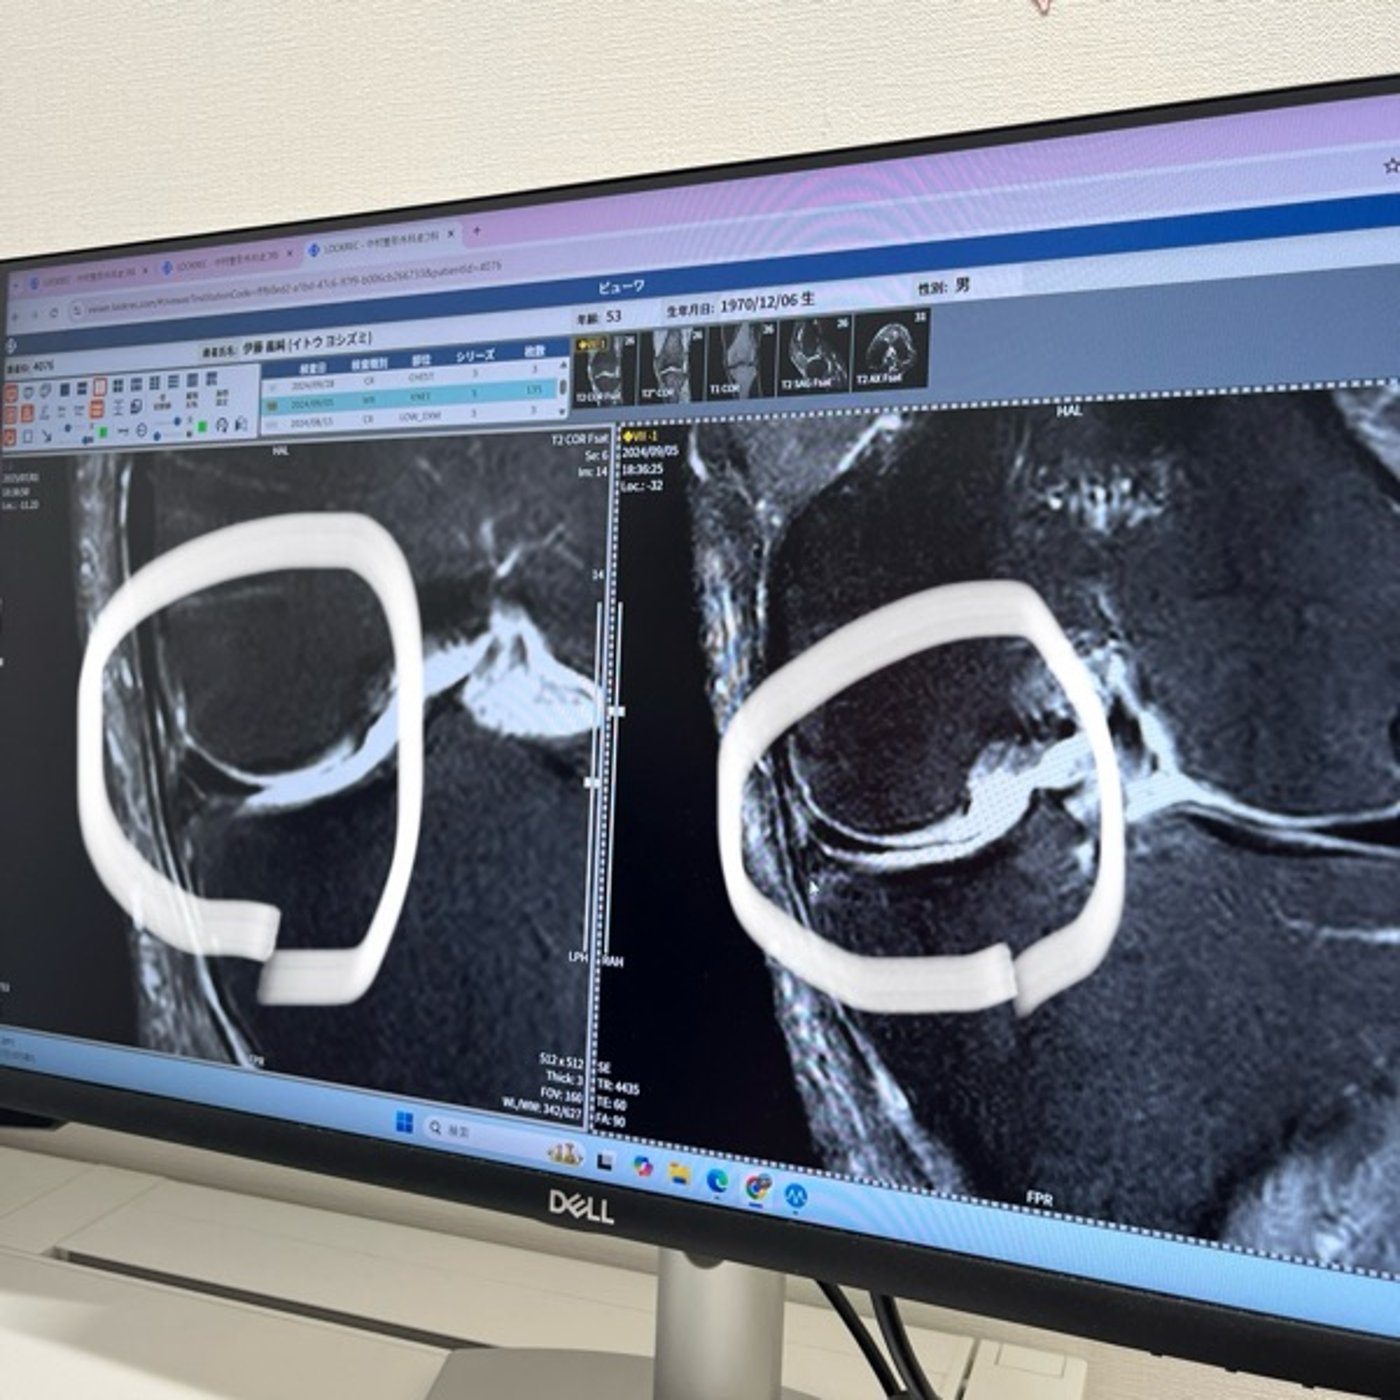

346 半月板関門通過!の話し

今日のラジオ📻はMRI検査結果の報告て半月板とは?ちについてです🤓